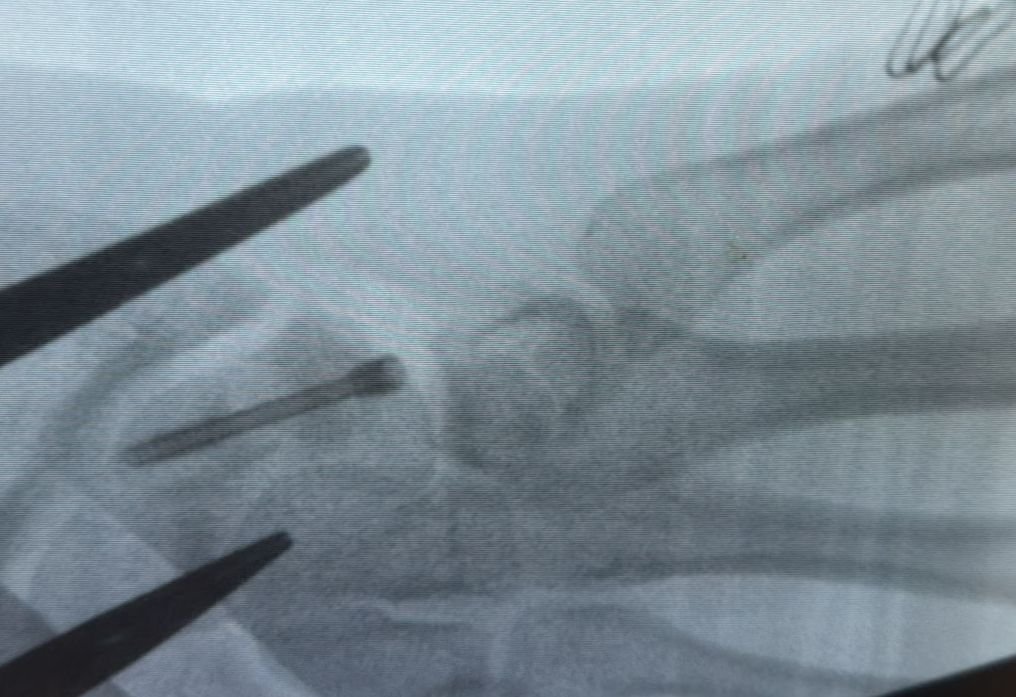

A részletes képalkotó vizsgálatok alapján dr. Alexandru Pîrvan szakorvos jobb oldali sajkacsonttörést állapított meg, amely nem forrt össze, és álízület (pseudoarthrosis) alakult ki, részleges szalagsérüléssel társulva.

Fotó: Bihar megyei kórház

A rendkívül ritka kórképet december végén műtéti úton kezelték. Az operáció során a kialakult álízületet eltávolították, majd a csontot egy speciális, eltávolítást nem igénylő Herbert-csavarral stabilizálták. A közel két és fél órás beavatkozás sikeres volt, a beteg állapota kedvezően alakult, és a felépülés jól halad, fogalmaznak a közleményben.